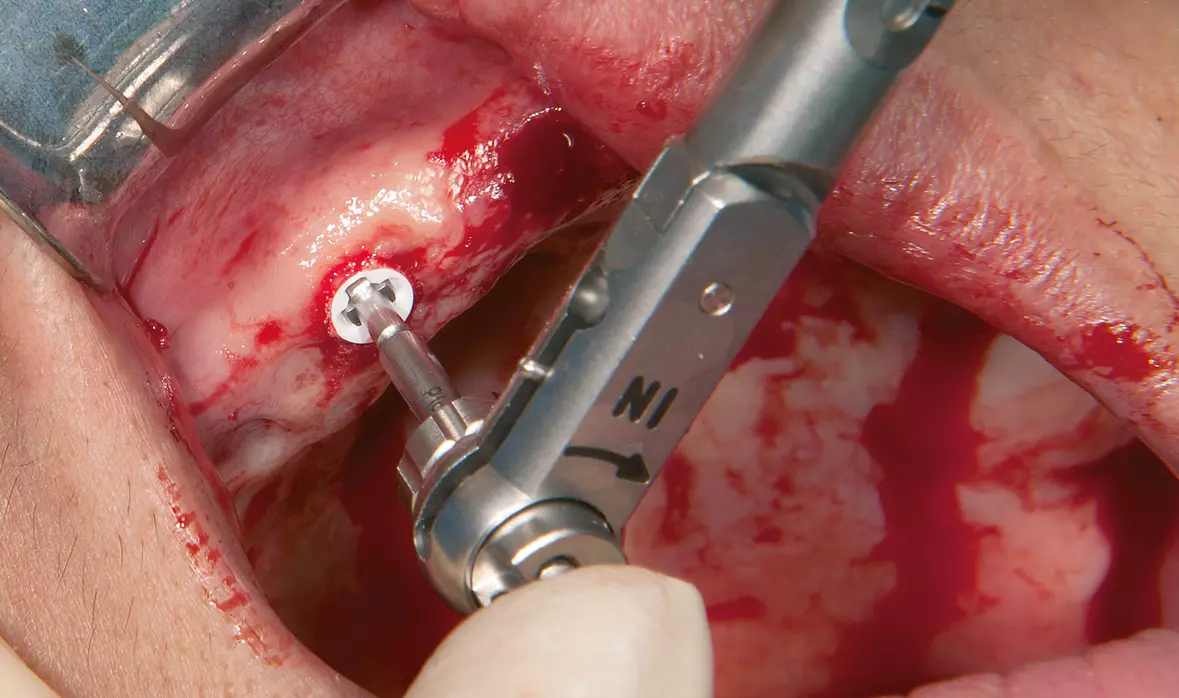

Abb. 16: Manuelles Eindrehen des Implantates. Dr. Michael Leistner

Abb. 16: Manuelles Eindrehen des Implantates.

Abb. 17: Nachziehen mit dem Drehmomentschlüssel (max. 35 N/cm). Dr. Michael Leistner

Abb. 17: Nachziehen mit dem Drehmomentschlüssel (max. 35 N/cm).